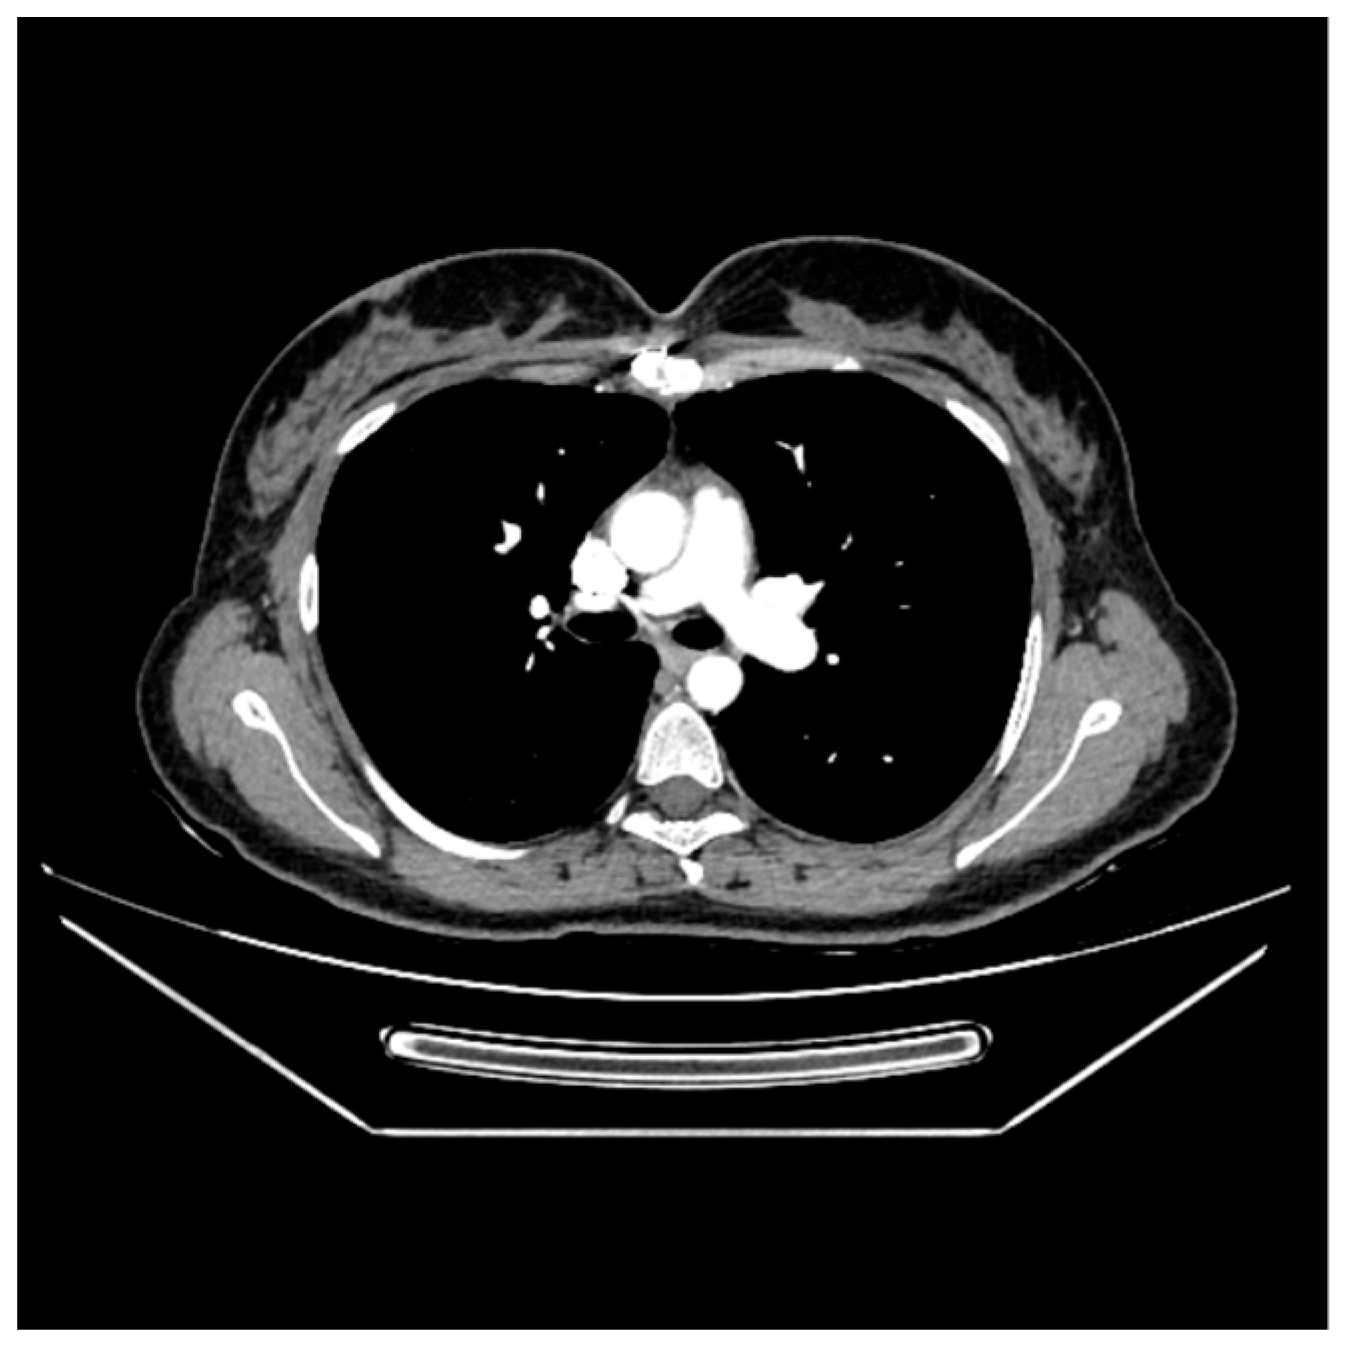

2. Case Report